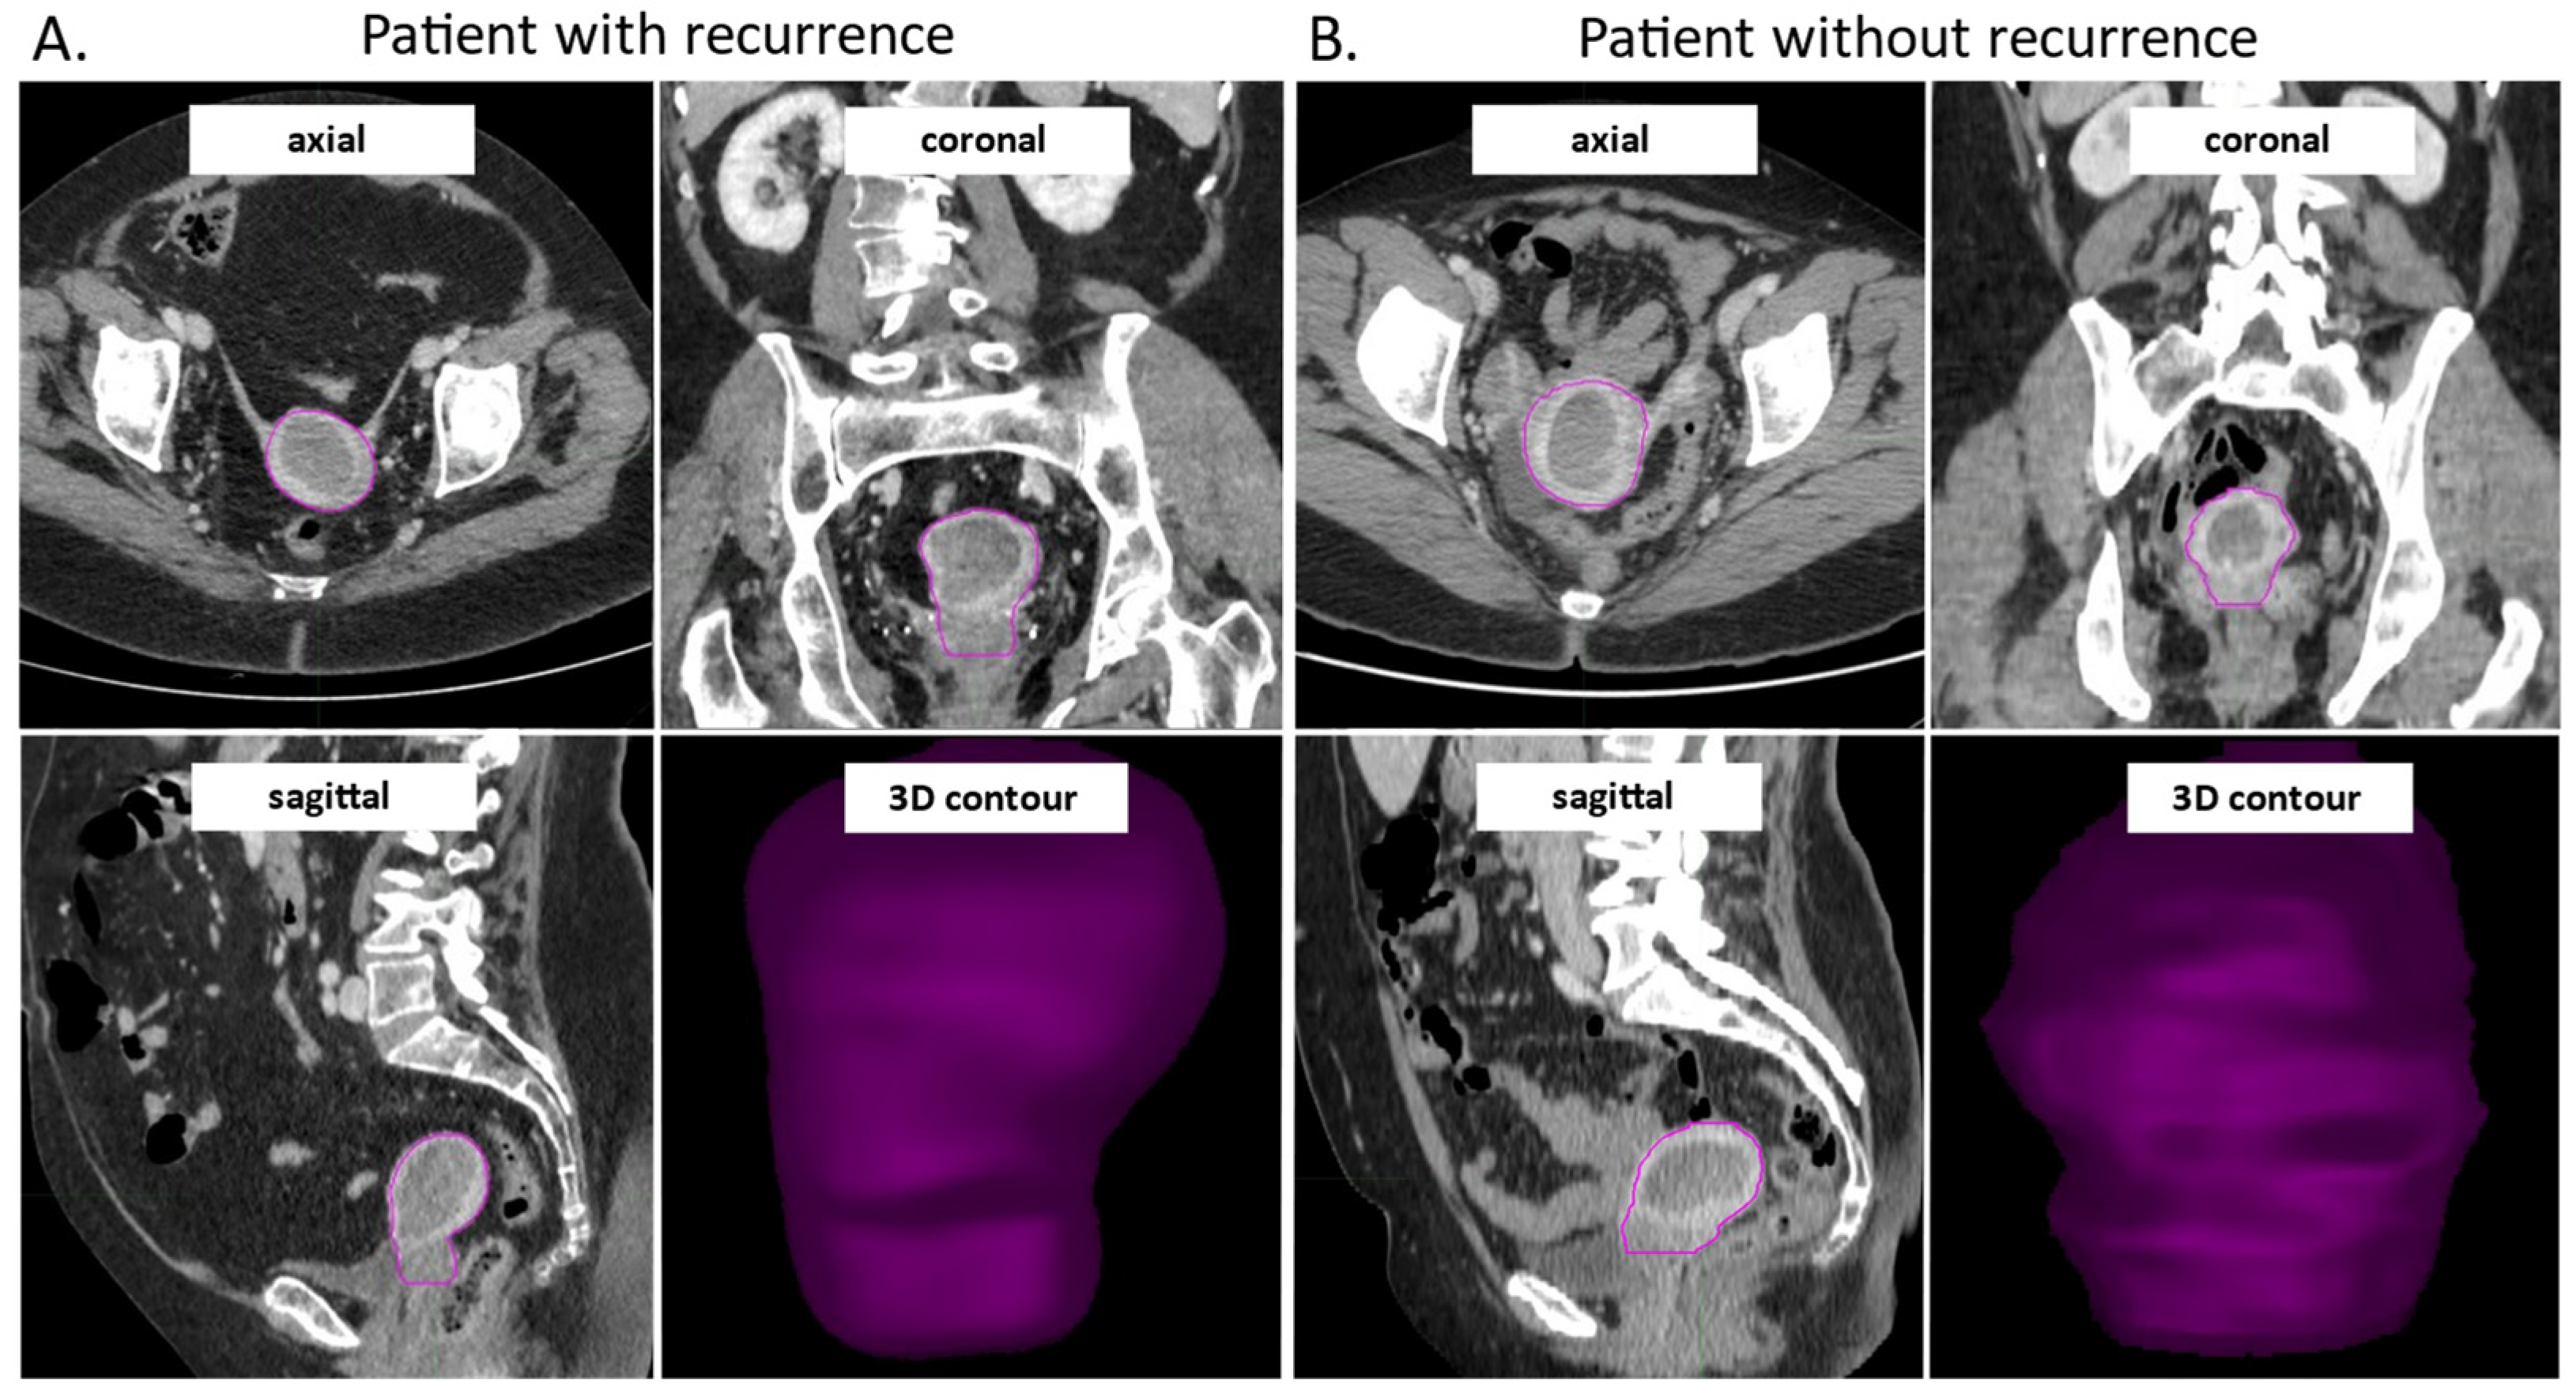

2.2. Patients CT Scans, Image Selection and Contouring